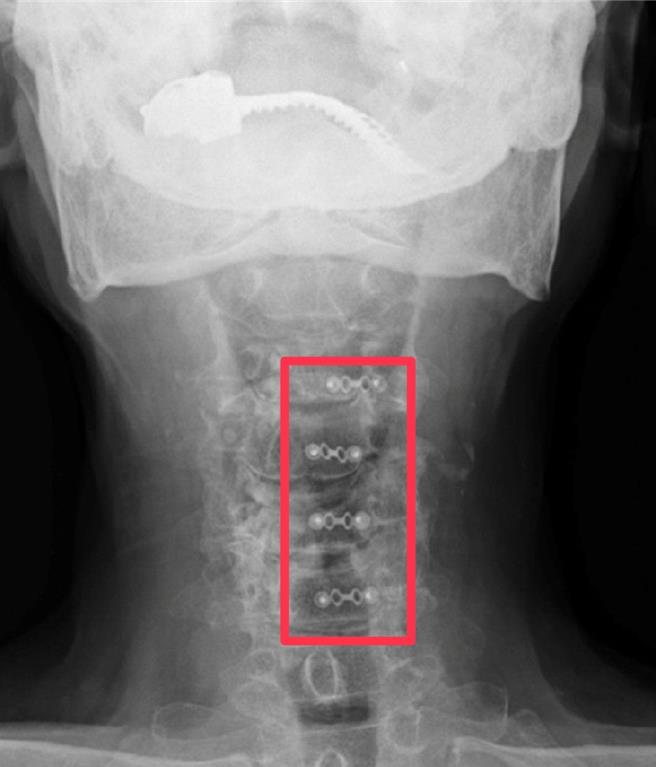

透过颈椎核磁共振检查,赫然发现老翁的颈椎管腔多节段严重狭窄还合併脊髓受伤。(部苗医院提供/李京升苗栗传真)

王姓老翁数月前前往到卫福部苗栗医院求诊鱼苗神经外科医师吴圣文,医师发现王翁脊椎有着明显退化,接着每周1次接受施打剂量维他命B12点滴,但其麻痹状况有限,进一步安排颈椎核磁共振检查,赫然发现老翁的颈椎管腔多节段严重狭窄还合併脊髓受伤。

吴圣文表示,该手术方式是病人在麻醉后,会俯卧和用头钉固定头部,伤口在颈椎后方,利用神经外科高倍显微镜,将压迫严重的节段椎板打开,就像把家里的后门打开一样,藉此扩大脊髓腔让脊髓获得充分的减压空间,再用骨板把打开的椎板固定。

他说,这项手术可以一次治疗多节段的颈椎狭窄问题,又比一般的椎板全切除术破坏较少,也可以减少日后颈椎变形的病发症。王姓老翁手术当天只花3小时,出血量极小,术后由原定安排的加护病房观察,在神经外科团队及开刀麻醉团队的精密治疗下,也直接回一般病房休养,术后第2天随即下床行走,第3天后拔掉引流管就出院休养了。